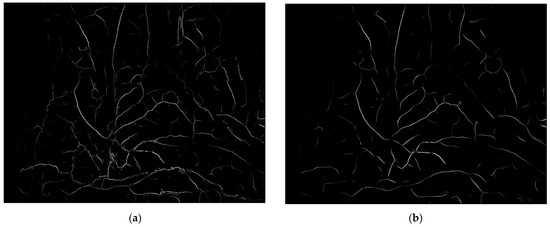

where Iridge represents ridge degree. As shown in Figure 6, (a) is the enhancement result of the Frangi enhancement method, and (b) is enhancement result of this paper method. The blood vessels after single-pixel transformation are thinner and have clearer branches compared to the original method blood vessel images in the human lumen.

Figure 6.

Enhancement results of vascular structure enhancement: (a) the Frangi enhancement method; (b) the method proposed in this paper.